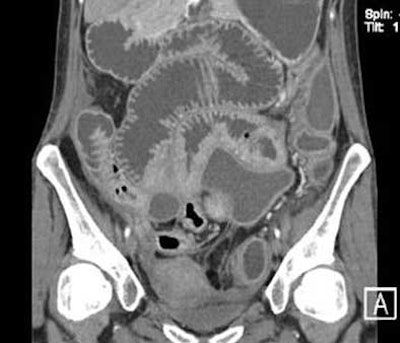

![]() |

| Top and below: In same 21-year-old patient, axial CT enteroclysis shows long-segment inflammatory reaction and severe thickening of the terminal and preterminal ileum due to histologically proven Crohn's disease. Bottom image, equivalent coronal multiplanar reformation. |